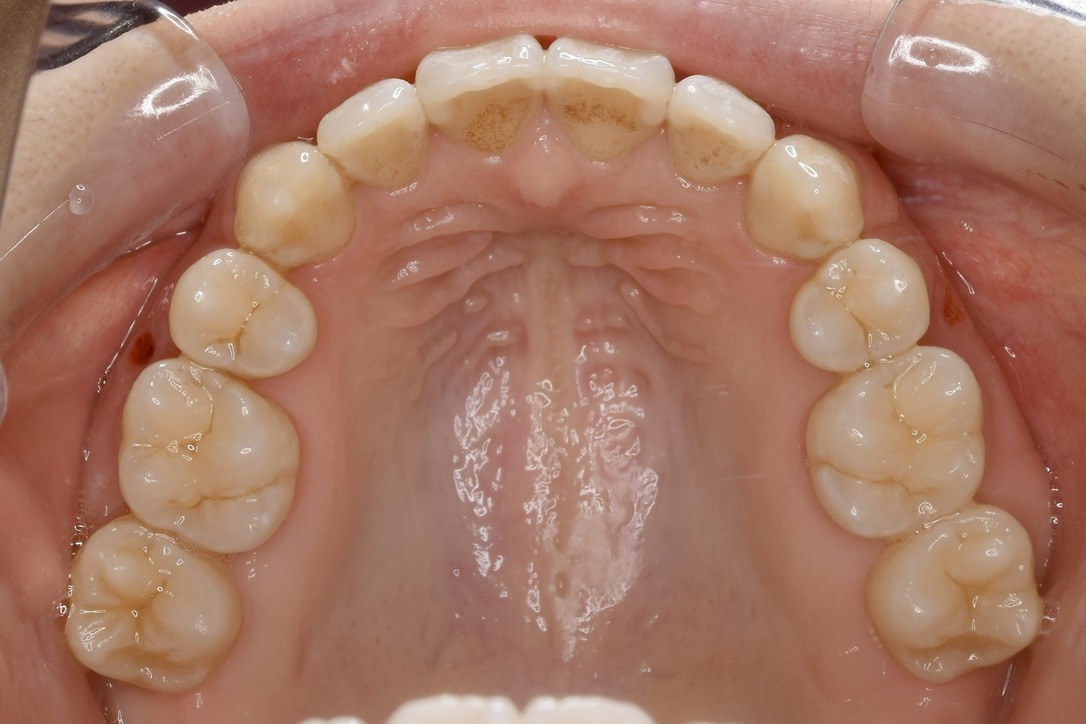

上あご 内側

| 主訴 | 上の歯が前に出ている気がして気になる。 |

|---|---|

| 診断名・主な症状 | 叢生 |

| 年齢 | 23歳 |

| 治療内容 | 上の奥歯を後ろに引くことでできたスペースを利用して前歯のデコボコを解消しました。 |

| 使用装置 | 舌側矯正(ワイヤー) 表側矯正(ワイヤー) 矯正用ミニインプラント |

| 抜歯部位 | 抜歯なし |

| 治療期間 | 1年9ヶ月 |

| 通院回数 | 24回 |

| 費用 | 120万円程度(税別) 231 |

| リスク・副作用 | 痛み、歯肉退縮、歯根吸収、抜歯に伴う出血や腫れが生じることがあります。 |